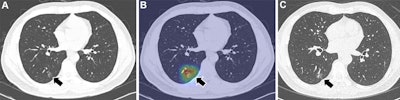

Examples of Sybil, an open-source deep learning model, correctly predicting lung cancers (visible lung cancer at baseline CT). (A) Axial low-dose CT image of the lungs in a 54-year-old heavy-smoking man shows a 1.5-cm subsolid nodule in the right lower lobe, with the (B) attention map focusing on this area (arrow). The Sybil lung risk scores were 13.1% for 1-year risk, 20.2% for 2-year risk, 20.7% for 3-year risk, 23.6% for 4-year risk, 24.8% for 5-year risk, and 31.2% for 6-year risk. (C) Axial CT image after two years shows that the subsolid nodule had grown to 2 cm and was subsequently diagnosed as adenocarcinoma (arrow). The Sybil lung risk score is a deep learning-based risk score for predicting future lung cancer risk within 6 years from a low-dose chest CT scan.Radiology and Jong Hyuk Lee, MD, PhD.